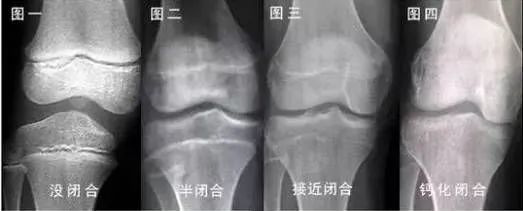

骨龄检测是通过观察骨化中心的大小、形态、结构和相互关系的变化来判断体格和生理的发育程度。

1、3-15岁为骨龄评估最佳年龄段。3岁以下的婴幼儿由于骨化中心还没有出全,除非是怀疑有重大疾病需要检查,否则不建议常规监测;而大部分男孩在16-17岁、女孩在14-15岁,骨骺线会完全闭合,基本丧失了长高的潜能,评估意义不大。